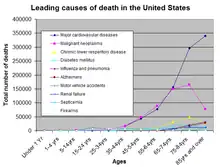

Risk for severe COVID-19 increases with age, disability, and underlying medical conditions. The SARS-CoV-2 Omicron variant is more infectious but has been associated with less severe disease.

In-hospital mortality among patients hospitalized primarily for COVID-19 decreased from 15.1% (Delta period) to 4.9% (later Omicron period; April–June 2022), despite high-risk patient groups representing a larger proportion of hospitalizations. During the later Omicron period, the majority of in-hospital deaths occurred among adults aged ≥65 years (81.9%) and persons with three or more underlying medical conditions (73.4%).

- For months, scientists have observed trends showing older people and men tend to be more vulnerable. Scientists know something about why children tend to have less serious infections from coronavirus -- they have fewer ACE2 receptors in their noses, and these receptors are how coronavirus gets into our cells. But they can't really explain why older people have such a high death rate from coronavirus -- much higher than from the common flu.

"What is it about age that makes you so much more susceptible to having disease?" Collignon questioned. "We've got the data and we know it's true ... but I don't think we've got all the answers for that."- Peter Collignon, as quoted in “Coronavirus has been with us for a year. Here's what we still don't know”, by Julia Hollingsworth, CNN, (28/12/2020)